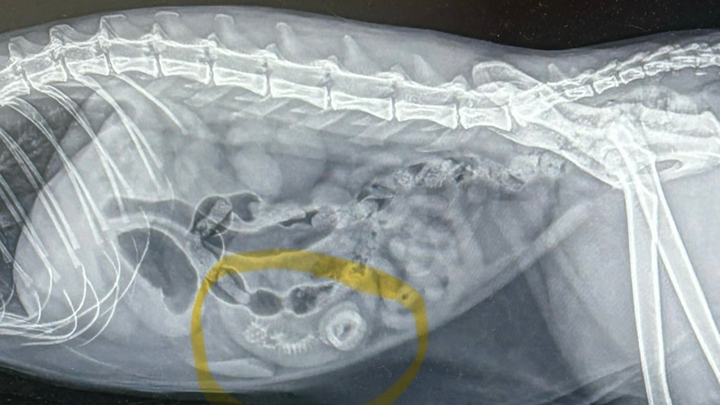

Hi, my name is Sarah and I have a 4-year-old spunky cat named Spence. Spence has recently gotten into things he shouldn’t and now needs to have surgery to remove objects in his intestines! This surgery is going to cost about $8,600 as he needs to be seen at VEG in Shrewsbury! No one likes to ask for help, but my spunky boy still has so much life to live! Any and all monetary help, likes, shares, and word of mouth helps! Donations go toward payment of surgery. Thank you for taking the time to read and care about Spence!